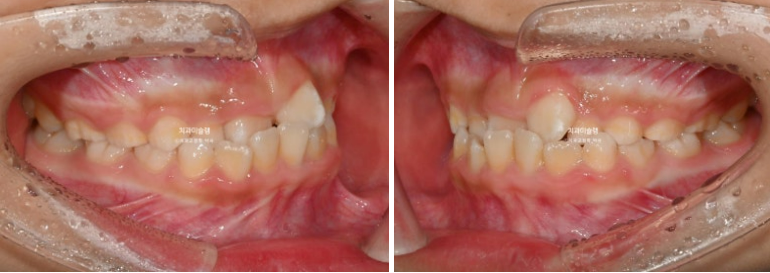

두달 후 앞니 반대교합이 해소가 되어 왔습니다.

25.06

덧니처럼 배열에서 벗어나있던 앞니가 꽤 제자리로 들어온 것이 보이죠?

프리올소는 앞니 배열을 완벽하게 하지는 않지만 약간은 잡아주는 효과도 있습니다.